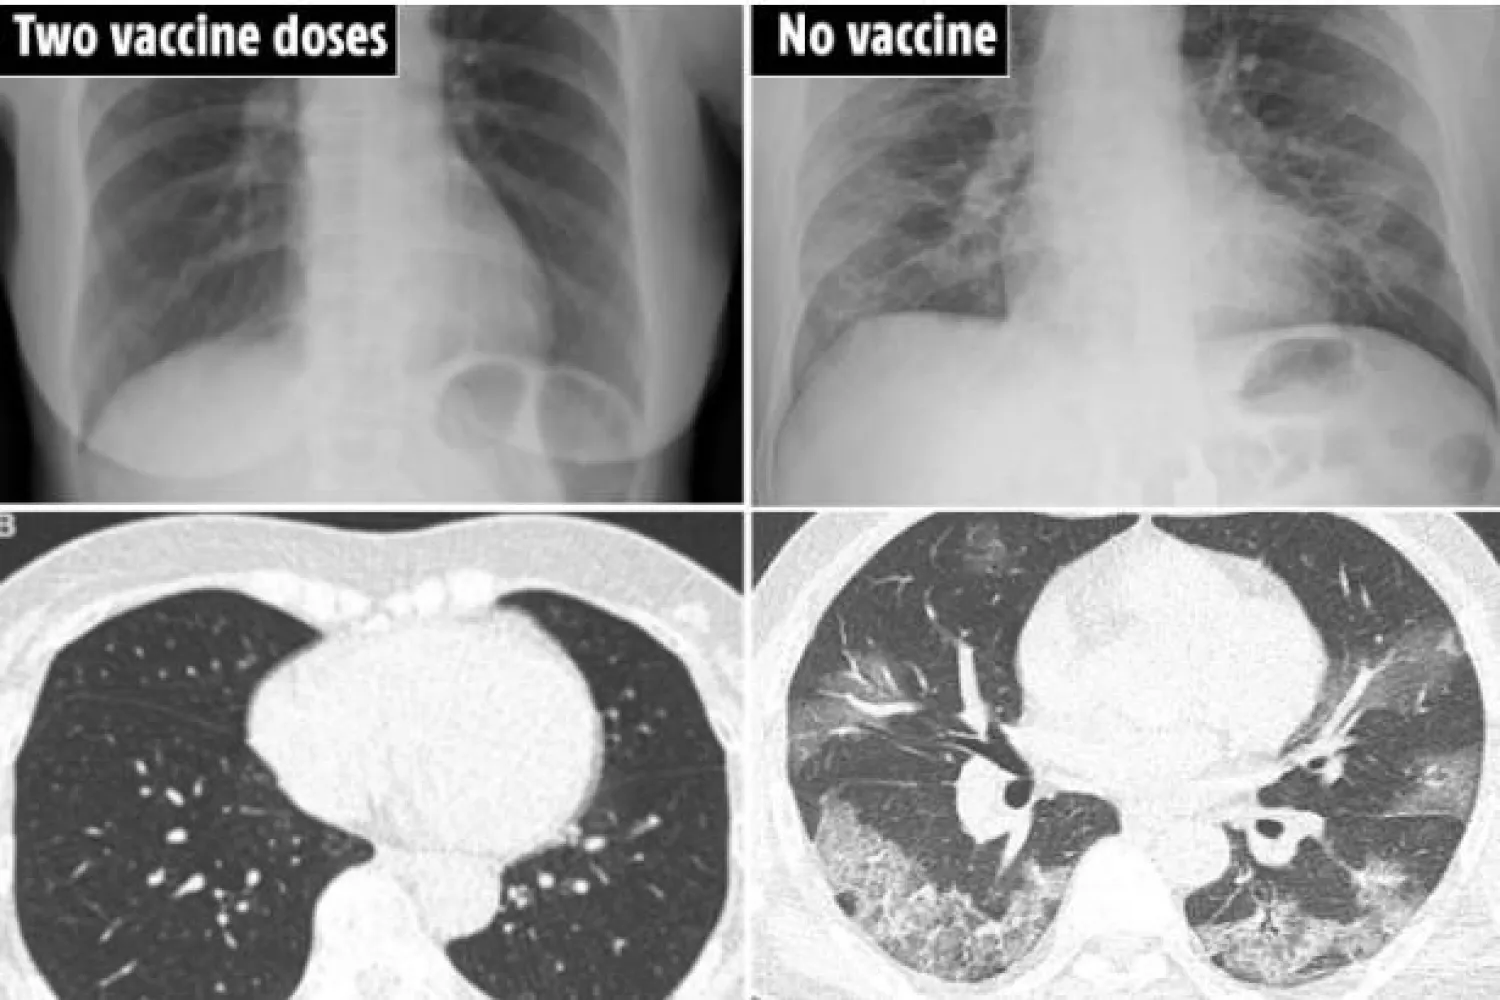

كشفت صور صادمة لأشعات مقطعية على الرئة مدى أهمية الحصول على لقاحات فيروس كورونا.

وبحسب صحيفة «ذا صن» البريطانية، فإن الصور التي نشرها باحثون من مستشفى جامعة بوسان الوطنية في كوريا الجنوبية، تظهر التغيرات التي حدثت في رئتي 4 مرضى مختلفين عندما أصيبوا بكورونا.

وشملت الصور الأشعة المقطعية لرئة مريضة تبلغ من العمر 65 عاماً، أصيبت بعدوى كورونا بعد شهرين من تلقي جرعتي لقاح فايزر، وأخرى لمريض يبلغ من العمر 48 عاماً أصيب بالفيروس بعد شهر من تلقي جرعة واحدة من لقاح أسترازينيكا، وأشعة ثالثة لمريض يبلغ من العمر 36 عاماً لم يتلق اللقاح إطلاقاً ولم يكن يعاني من أي مشكلات صحية قبل إصابته بالعدوى، وأشعة لمريض يبلغ من العمر 58 عاماً ولم يتلق اللقاح رغم كونه مريضاً بالسكري وضغط الدم.

وفي الأشعة الأولى، ورغم كون المريضة تعاني من ارتفاع ضغط الدم، لم تظهر أي غيوم (عتامة) في الرئتين، كما لم يجد الخبراء أي أثر للالتهاب الرئوي - مما يدل على أن اللقاحات حالت دون إصابة المرأة بعدوى كورونا الشديدة.

أما في الأشعة الثالثة، فقد وجد الباحثون أثرا لعتامة شديدة بالرئتين، رغم كون المريض شابا لا يعاني من مشكلات صحية أساسية، إلا أن هذا نتج في الأغلب عن عدم تلقيه للقاح.

وكانت الأشعة الرابعة هي الأكثر إثارة للصدمة، حيث كانت رئتاه شديدتي العتامة، وأصيب بالتهاب رئوي شديد وكان لديه نقص شديد بالأكسجين وقد دخل إلى وحدة العناية المركزة.

أشعة لمريضة تلقت جرعتي اللقاح (يسار) وأخرى لمريض لم يتلقِ اللقاح تماماً (يمين) (ذا صن)